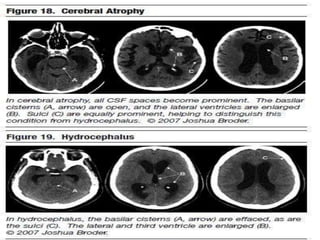

Disoders of CSF spaces

Disoders of CSFspaces • Hydrocephalus communicating and non communicating including IIH,NPH. • Loss of csf spaces usually secondary to degenerative and other secondary processes.